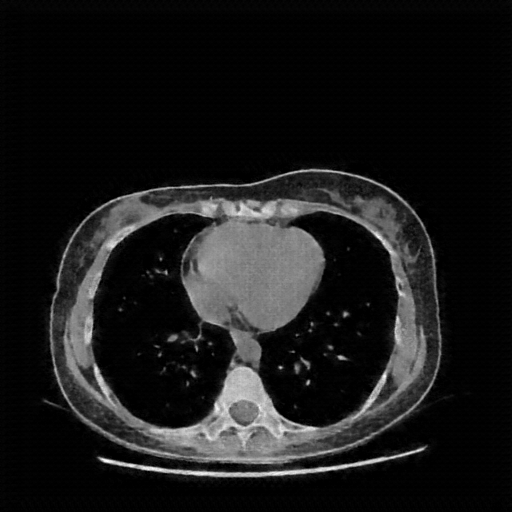

Original VENOUS CT scan

Lung window (WL -600, WW 1500 β†’ Low βˆ’1350, High +150)

Actual HU range: [-160.0, 150.0]